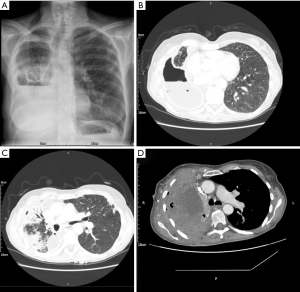

Buttressing of the stump with a tension-free vascularized pedicled flap (46,62) should be considered. This aims to increase the blood supply to the stump and has been described using intercostal (63), latissimus dorsi (64,65) or serratus anterior muscle flaps (66,67), pectoralis major and diaphragm flaps (46,68), omentopexy (69,70) thymic flap (71), pericardial fat pad (72) and pleural flap (73). Figure 2 shows CT images of a patient who developed BPF following bilobectomy. Re-operation, primary closure, buttressing with intercostal muscle, obliteration of the pleural space using pedicled serratus anterior and pectoralis muscle flap was performed. Where the above techniques fail, open window thoracostomy can be considered for management of sepsis if mediastinum is fixed. Thoracoplasty may be considered for recurrent cases. Operative mortality is 3.8% to 5.1% (57,74) with surgical cure rates between 88–90% (57,75).